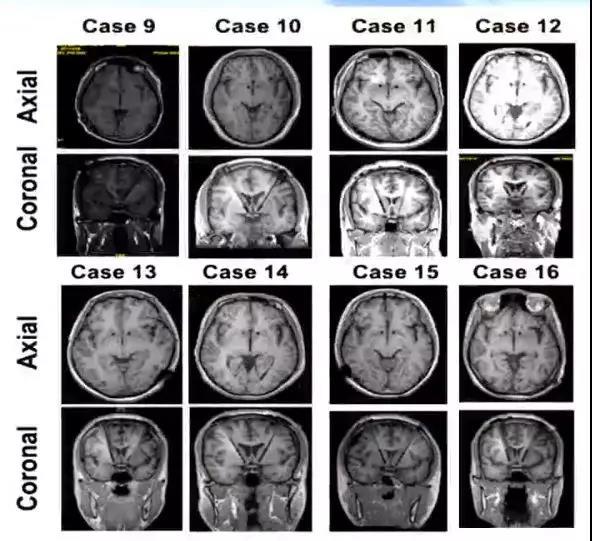

2014.03-2016.05,16名受试者接受DBS手术,其中11名植入自制国产DBS系统,5名植入进口加长电极DBS系统。11名受试者操守时间已超过2年,单病例最长操守时间已超过4年。截至目前,仅有4例复吸,1例失随访,仅占全部受试者的31.3%。

1. 结果-术后MRI复查电极位置